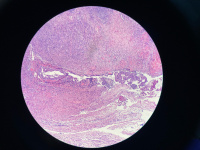

卵巢非典型内膜异位?

性别

女

年龄

49

临床诊断

子宫肌瘤

一般病史

无

标本名称

全子宫双附件

大体所见

附件未见特殊

病灶就这些,请教诊断

图3

像子宫内膜异位